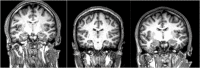

In this review article we have consolidated the imaging literature of patients with schizophrenia across the full spectrum of modalities in radiology including computed tomography (CT), morphologic magnetic resonance imaging (MRI), functional magnetic resonance imaging (fMRI), magnetic resonance spectroscopy (MRS), positron emission tomography (PET), and magnetoencephalography (MEG). We look at the impact of various subtypes of schizophrenia on imaging findings and the changes that occur with medical and transcranial magnetic stimulation (TMS) therapy. Our goal was a comprehensive multimodality summary of the findings of state-of-the-art imaging in untreated and treated patients with schizophrenia. Clinical imaging in schizophrenia is used to exclude structural lesions which may produce symptoms that may mimic those of patients with schizophrenia. Nonetheless one finds global volume loss in the brains of patients with schizophrenia with associated increased cerebrospinal fluid (CSF) volume and decreased gray matter volume. These features may be influenced by the duration of disease and or medication use. For functional studies, be they fluorodeoxyglucose positron emission tomography (FDG PET), rs-fMRI, task-based fMRI, diffusion tensor imaging (DTI) or MEG there generally is hypoactivation and disconnection between brain regions. However, these findings may vary depending upon the negative or positive symptomatology manifested in the patients. MR spectroscopy generally shows low N-acetylaspartate from neuronal loss and low glutamine (a neuroexcitatory marker) but glutathione may be elevated, particularly in non-treatment responders. The literature in schizophrenia is difficult to evaluate because age, gender, symptomatology, comorbidities, therapy use, disease duration, substance abuse, and coexisting other psychiatric disorders have not been adequately controlled for, even in large studies and meta-analyses.